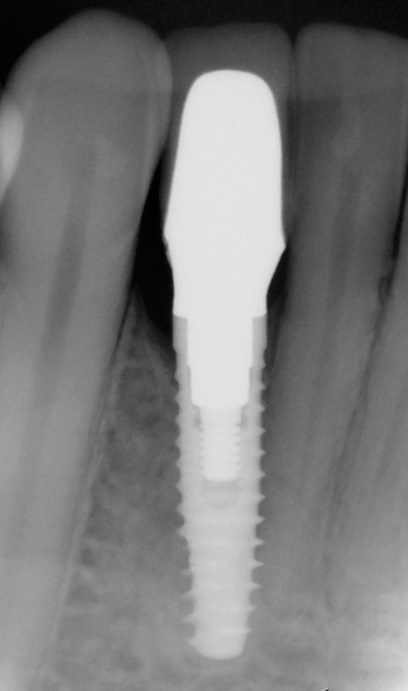

Fig 1. Midfacial recession can affect the esthetics of a smile and lead to an unsatisfactory outcome.

Fig 2. The cause for midfacial recession is excessive labial implant placement. Secondary to poor placement is overcontouring of the implant abutment.

Fig 13. The final radiograph of the seated crown showing a healthy bone level around the implant.

Figure 13